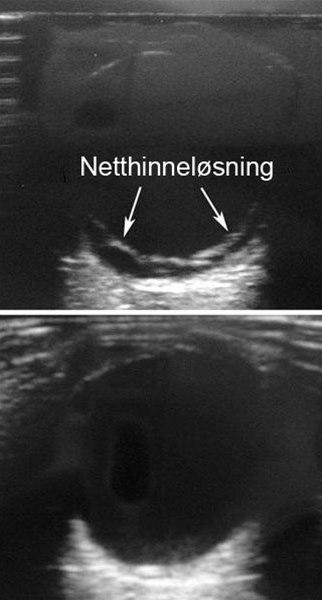

Netthinneløsning demonstrert med ultralyd

netthinneløsning ultralyd